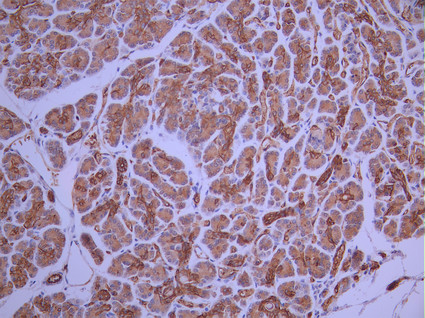

IHC image of CSB-RA975044A0HU diluted at 1:100 and staining in paraffin-embedded human pancreatic tissue performed on a Leica BondTM system. After dewaxing and hydration, antigen retrieval was mediated by high pressure in a citrate buffer (pH 6.0). Section was blocked with 10% normal goat serum 30min at RT. Then primary antibody (1% BSA) was incubated at 4°C overnight. The primary is detected by a Goat anti-rabbit polymer IgG labeled by HRP and visualized using 0.05% DAB.